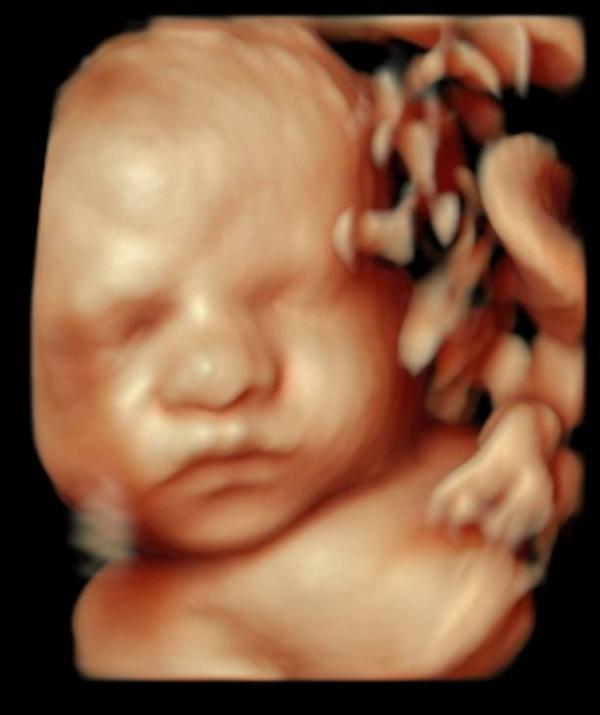

31 неделя 3д фото